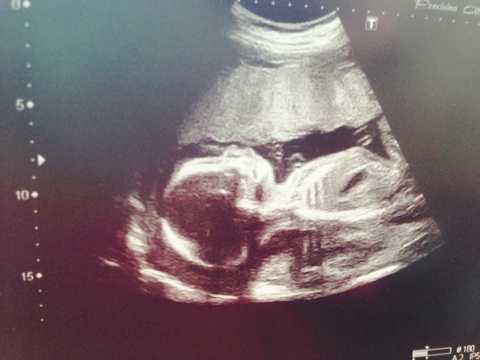

И еще мне нравится фото улыбочки))) такие прям снимки хорошие))) а у нас сынок спал, еще и попой отвернулся, ножки поджал-еле подлезла узистка чтобы рассмотреть кто там и лицо ручками закрыл.. Как мы его ее тормошили и на бок я ложилась, и начитавшись поела перед узи сладкое-неа-пофиг ему-спал)))

Я поела перед узи пюре с котлетой и сладкий чай) и сразу на узи! Так он показал себя со всех сторон! Даже узистка говорила, что очень хорошо позировал!) значит у вас тихий час был..)